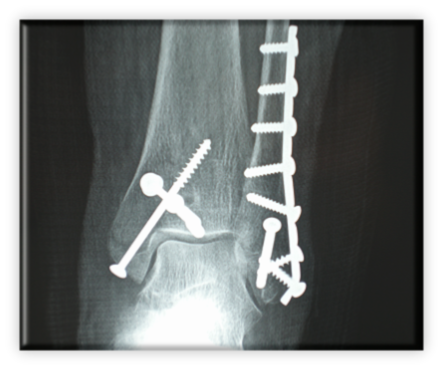

Πρόκειται για αρκετά σοβαρό τραυματισμό, αφού το κάταγμα επεκτείνεται στην άρθρωση (ενδαρθρικό) με συνέπεια αυξημένα ποσοστά μετατραυματικής αρθρίτιδας της ποδοκνημικής. Αυτό καθιστά την ακριβή ανάταξη της αρθρικής επιφάνειας επιβεβλημένη. Ειδικότερα, αν το κάταγμα οπισθίου σφυρού περιλαμβάνει το 1/3 ή περισσότερο της αρθρικής επιφάνειας πρέπει να αναταχθεί και οστεοσυνθεθεί. Τα συνυπάρχοντα κατάγματα του κάτω πέρατος της περόνης (έξω σφυρό) και κάτω έσω πέρας της κνήμης (έσω σφυρό) καθιστούν την άρθρωση  εξαιρετικά ασταθή. Η όλη κατάσταση μπορεί να παρομοιαστεί με ένα τρίποδα του οποίου έχουν σπάσει και τα τρία πόδια. Φτιάχνοντας το ένα ή τα δύο μόνο πόδια, δεν μπορεί να έχει ισορροπία ο τρίποδας, οπότε πέφτει. Αντίστοιχα είναι τα πράγματα και για την άρθρωση της ποδοκνημικής που είναι μια στηρικτική άρθρωση.

Η θεραπεία είναι χειρουργική.